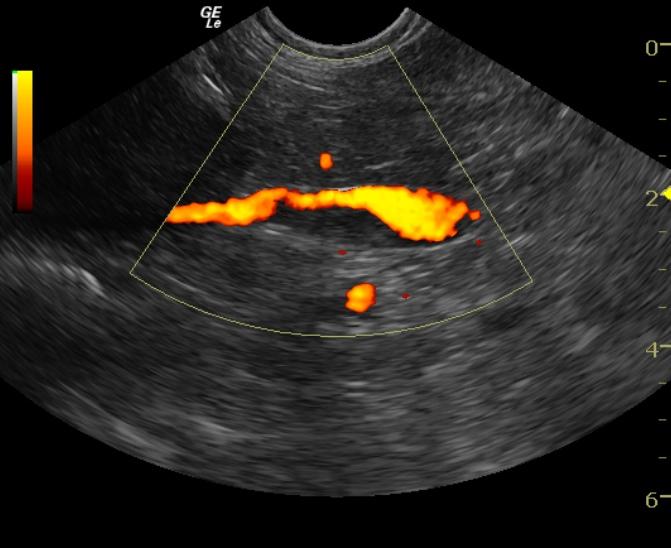

A 15-year-old FS mixed breed dog was presented for alopecia. On physical exam, her hair was found to be sparse and in patches along her dorsum. She was also mentally dull and appeared to be disoriented. Bilateral cataracts were present and there was a mild increase in the intraocular pressure measured bilaterally (tonometry measurement of 21 mm Hg). Blood chemistry revealed hyperphosphatemia, elevated ALT, elevated AST, and elevated GGT enzyme activities. The CBC, urinalysis, urine microalbumin, T4 and TSH were all within normal limits.

A 15-year-old FS mixed breed dog was presented for alopecia. On physical exam, her hair was found to be sparse and in patches along her dorsum. She was also mentally dull and appeared to be disoriented. Bilateral cataracts were present and there was a mild increase in the intraocular pressure measured bilaterally (tonometry measurement of 21 mm Hg). Blood chemistry revealed hyperphosphatemia, elevated ALT, elevated AST, and elevated GGT enzyme activities. The CBC, urinalysis, urine microalbumin, T4 and TSH were all within normal limits. A chemistry profile was repeated and showed persistence of the hyperphosphatemia, increased liver enzymes (ALT, AST, GGT) and hyperglobulinemia.